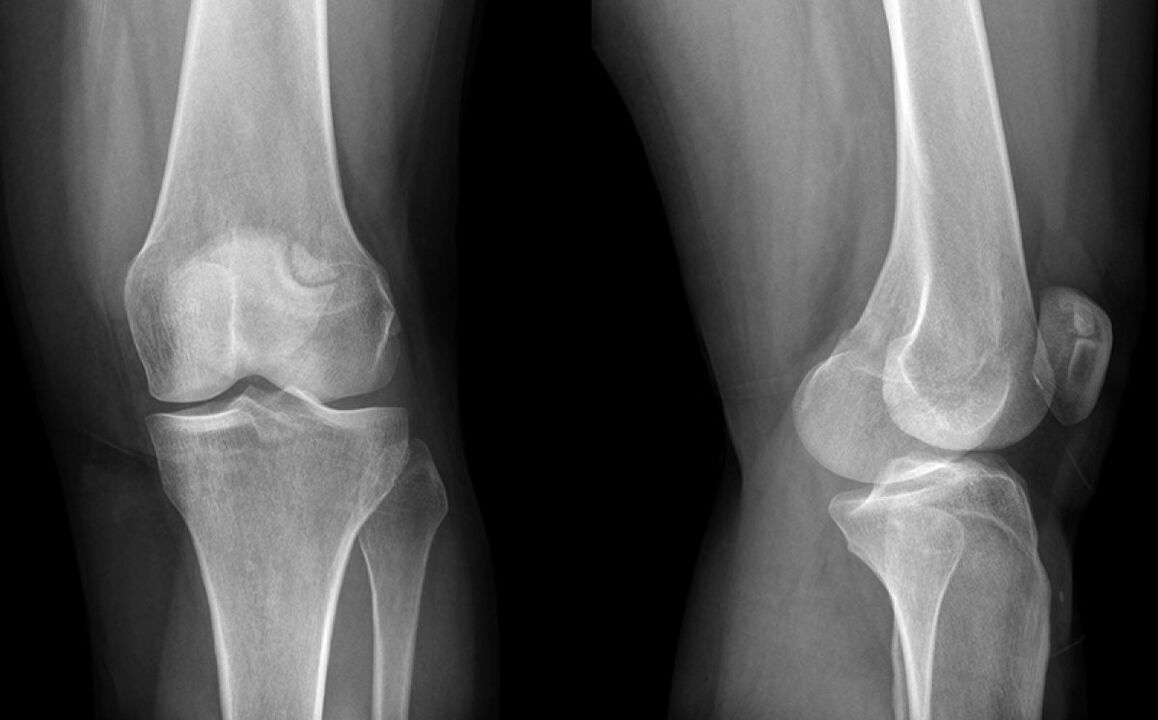

Koljeno je boljelo tri tjedna. U konačnici sam otišao kod liječnika koji je sumnjao na štetu meniskusu i poslao u X -trag. Dijagnoza je početna stadija artroze zgloba koljena.